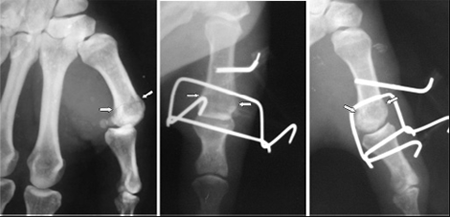

Рис. 1. Этапы наложения системы

Остеосинтез при переломах костей кисти должен соответствовать анатомо-функциональным особенностям скелета кисти, отличаться атравматичностью, обладать достаточной стабильностью, не ограничивать раннюю активную функцию суставов кисти и пальцев [5]. Методика хирургического лечения переломов шейки и головки пястных костей разрабатывалась нами в соответствии с общими принципами наружного чрескостного остеосинтеза: точное сопоставление отломков, малая травматичность вмешательства и высокая стабильность остеосинтеза, максимальное сохранение кровоснабжения поврежденной кости и сегмента конечности в целом, сохранение функции конечности, позволяющий обеспечивать функциональность больного с первых дней лечения. Мы предлагаем при переломах шейки и головки пястных костей использовать экстензион- ную систему Эйджи (Agee) (рис.1) [6]. Несмотря на то, что метод был разработан для лечения вывихов в межфаланговых суставах, нами, после модификации, система была адаптирована для лечения переломов пястных костей. Способ является малоинвазивным, технически легко выполняемым.

а. б. в.

Рис. 2. Фиксация перепомовывиха 1-ой пястной кости системой Эйджи. а. переломовывих 1-ой пястной кости б. и в. фиксация перелома и вправление вывиха системой

кости, у 8-и больных (34.78%) 1-ой, у 3 больных (13.05%) 2-ой пястной кости. У 19 больных (82.6%) наблюдались повреждения правой кисти. Объективное обследование проводилась по общепринятым методикам. Для диагностики характера повреждения костных структур пациентам выполнялась рентгенография травмированной кисти в двух стандартных проекциях. Всем была сделана операция с использованием экстензионной системы Эйджи (рис.2).